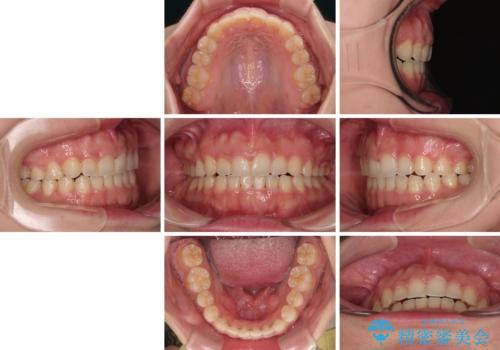

ワイヤー矯正でもインビザラインでも対応可能でしたが、上顎歯列が前方位であるときには、ワイヤー矯正の方がより良い仕上がりとなる可能性が高いため、ワイヤー矯正をおすすめいたしました。

舌の突出癖がなかなか改善されず、上下前歯が接触するようになるまでに長期間を要しました。